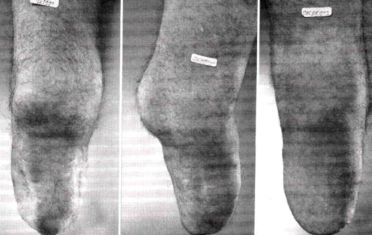

Developed about 1842 by James Syme, a leading Scottish surgeon, the Syme amputation leaves the long bones of the shank (the tibia and fibula) virtually intact, only a small portion at the very end being removed (Fig. 10). The tissues of the heel, which are ideally suited to withstand high pressures, are preserved, and this, in combination with the long bones, usually permits the patient to bear the full weight of his body on the end of the stump. Because the amputation stump is nearly as long as the unaffected limb, a person with Syme's amputation can usually get about the house without a prosthesis even though normal foot and ankle action has been lost. Atrophy of the severed muscles that were formerly attached to bones in the foot to provide ankle action results in a stump with a bulbous end which, though not of the most pleasing appearance, is quite an advantage in holding the prosthesis in place.

|

Since its introduction, Syme's operation has been looked upon with both favor and disfavor among surgeons. It seems to be the consensus now that "the Syme" should be performed in preference to amputation at a higher level if possible. In the case of most women, though, "the Syme" is undesirable because of the difficulty of providing a prosthesis that matches the shape of the other leg.